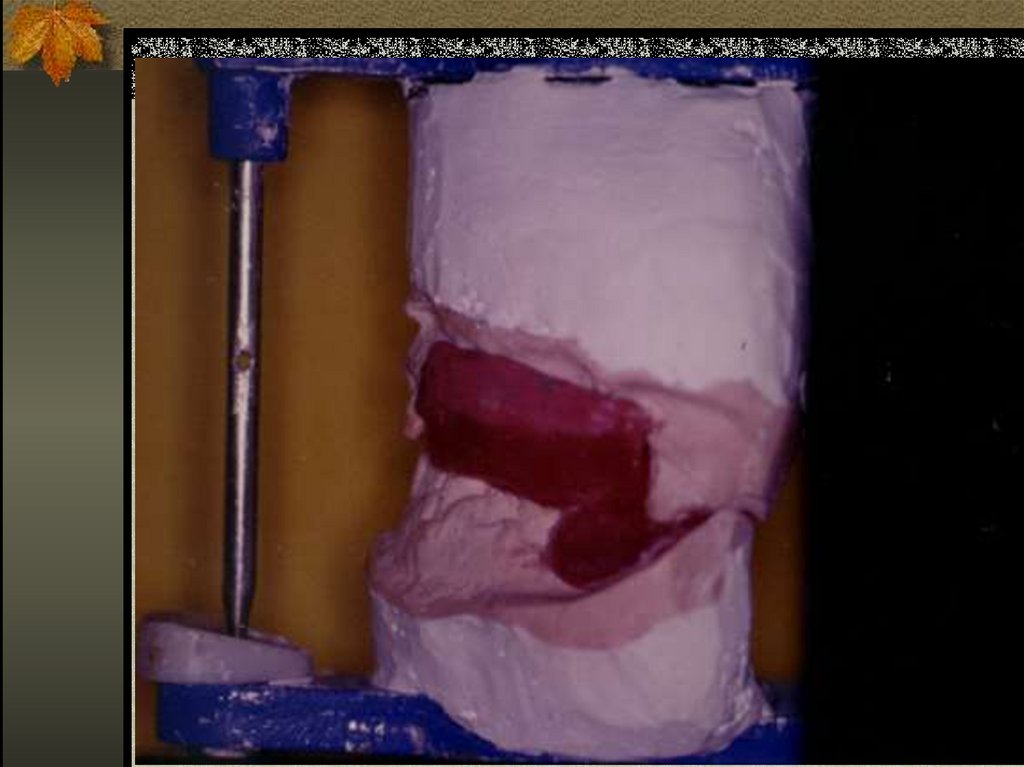

21. DÖKÜM REHBER APAREYİ

22. DAMAK PLAĞI ŞEKLİNDE REHBER APAREYİ